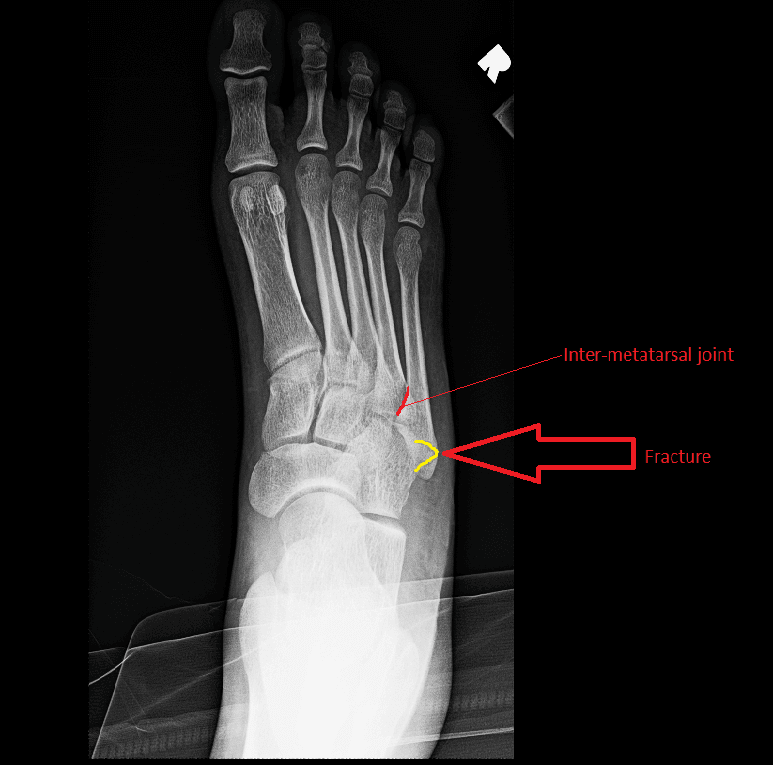

Area of your injury

Picture of bones in the foot

The main method of diagnosing fractures of this localization can be called radiography, which in most cases allows you to verify the diagnosis.

This type of fracture is one of the few diagnostics based on radiography, which in most cases allows to verify the diagnosis.

This type of fracture is one of the few diagnoses that are based on X-ray, which in most cases allows the diagnosis to be verified.

In all cases, the X-ray performed confirmed the diagnosis (Figure 1).